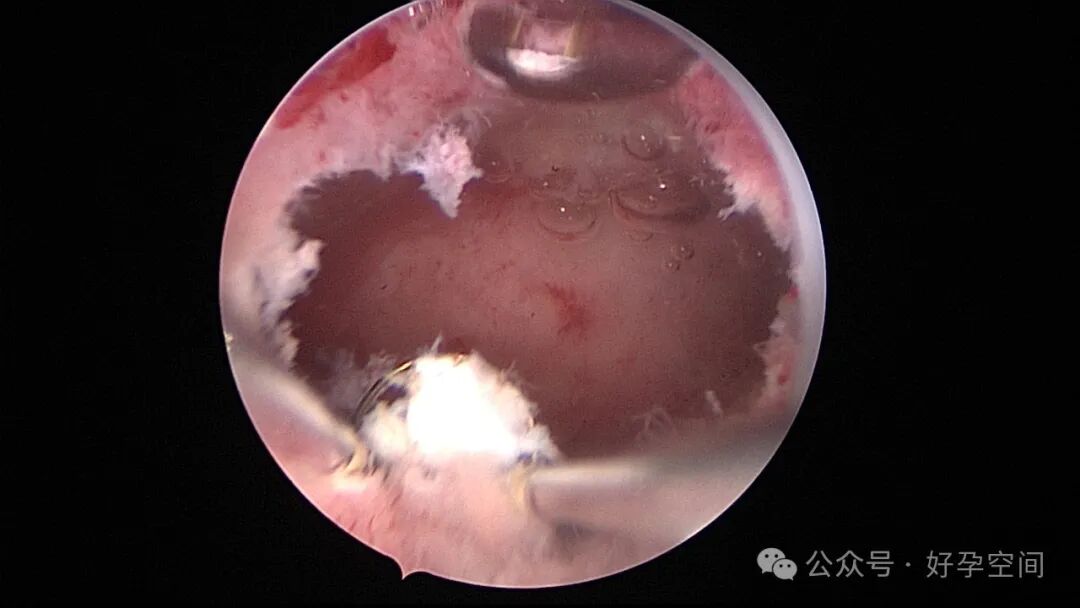

患者24岁,G6P3,顺产1次,双胎剖宫产1次。本次停经53天,计划外妊娠,行宫腔镜取胚及安环术。摘除胚胎后见宫腔右侧壁胚胎附着部位包块,约1.0cm*1.0cm*0.8cm,宫腔镜切除包块送病检,放置γ环一个,环两臂卷曲于右侧宫角,宫腔镜钩住环尾部下拉,上推节育环右臂,将环调整到正常位置。术后病检结果为“宫腔胎盘附着部位超常反应”。

超常胎盘部位(exaggerated placental site,EPS)反应是指在胎盘附着部位组织的过度反应性病变。1991年,WHO将其列入滋养细胞疾病,但目前国内外对该病的诊断尚无统一标准。在正常妊娠中,中间型滋养细胞可侵入底蜕膜或浅肌层,而超常胎盘部位反应时,中间型滋养细胞在胎盘部位大量浸润,并侵入子宫肌层,是正常胎盘反应的加剧,是一种滋养细胞疾病。EPS反应可发生于正常妊娠、流产或葡萄胎后,发生于葡萄胎者浸润力更为明显。EPS以病理诊断为依据,其组织学特征以中间型滋养细胞为主,由子宫内膜向肌层的良性漫润,不破坏原有组织结构,伴有淋巴细胞灶性浸润。EPS是一种非肿瘤性的良性滋养细胞疾病,普通人工流产、宫腔镜取胚或产后出血增多,手术医生主观感觉宫腔已经清理干净,但B超提示宫内占位包块,应考虑到是否存在EPS,建议做宫腔镜探查,切除包块送病检,以明确诊断,避免遗漏其他严重疾病,EPS对症治疗即可,观察病情变化,预后良好。